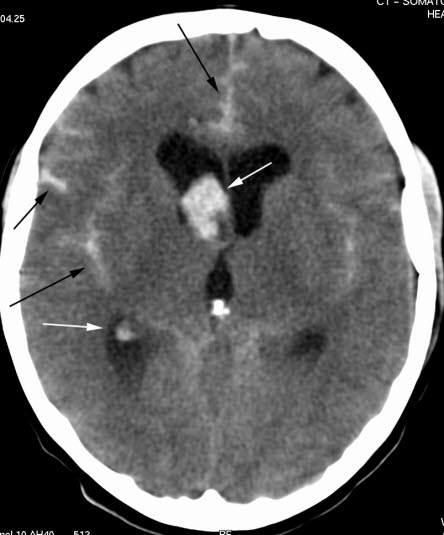

CT axialbilde uten kontrast

Blod (lyse områder) i høyre sideventrikkel (hvite piler), mellom hemisfærene frontalt og i fissura Sylvii på begge sider (svarte piler). Kalk i corpus pineale (intenst hvitt).